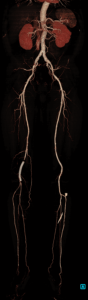

CONFIRA AS IMAGENS ABAIXO DO EXAME DE ANGIOTOMOGRAFIA VASCULAR.

Como podem ver, “conseguimos uma abrangência de vários segmentos do corpo em uma única aquisição!” – Angio Tomografia de Abdômen total e MMII (MEMBROS INFERIORES).